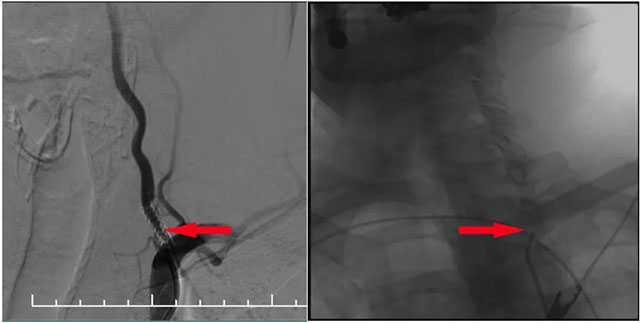

▲ DSA血管造影:左侧椎动脉支架内再狭窄

MR示双侧基底节区及右侧顶叶凸面小梗塞(部分软化灶形成)轻度脑白质疏松,MR-tof 可见左侧颈内动脉岩骨段狭窄。DSA血管造影:左侧椎动脉支架内再狭窄,左侧颈内动脉造影见岩骨段远端狭窄,右侧大脑中动脉由左侧颈内部分代偿,右侧颈动脉造影提示右侧颈内动脉闭塞。